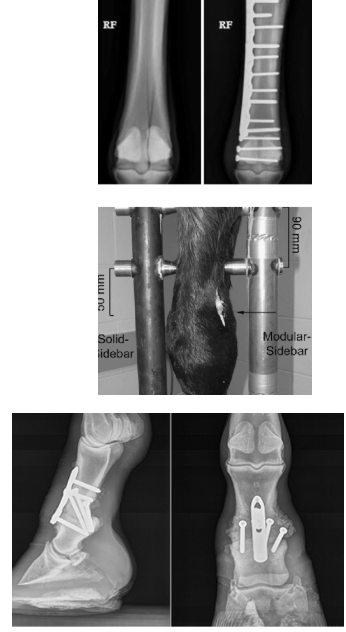

Fracture repair

Internal fixation: screws and/or plates attached directly to bone internally (permanent)

External fixation: support attached from outside body (temporary)

Joint fusion (arthrodesis)

Intentional fusion of a joint (normally joints that don't move a lot in general)

Treatment for articular fractures, osteoarthritis, or other instability

Remove cartilage and immobilize joint until bones fuse together